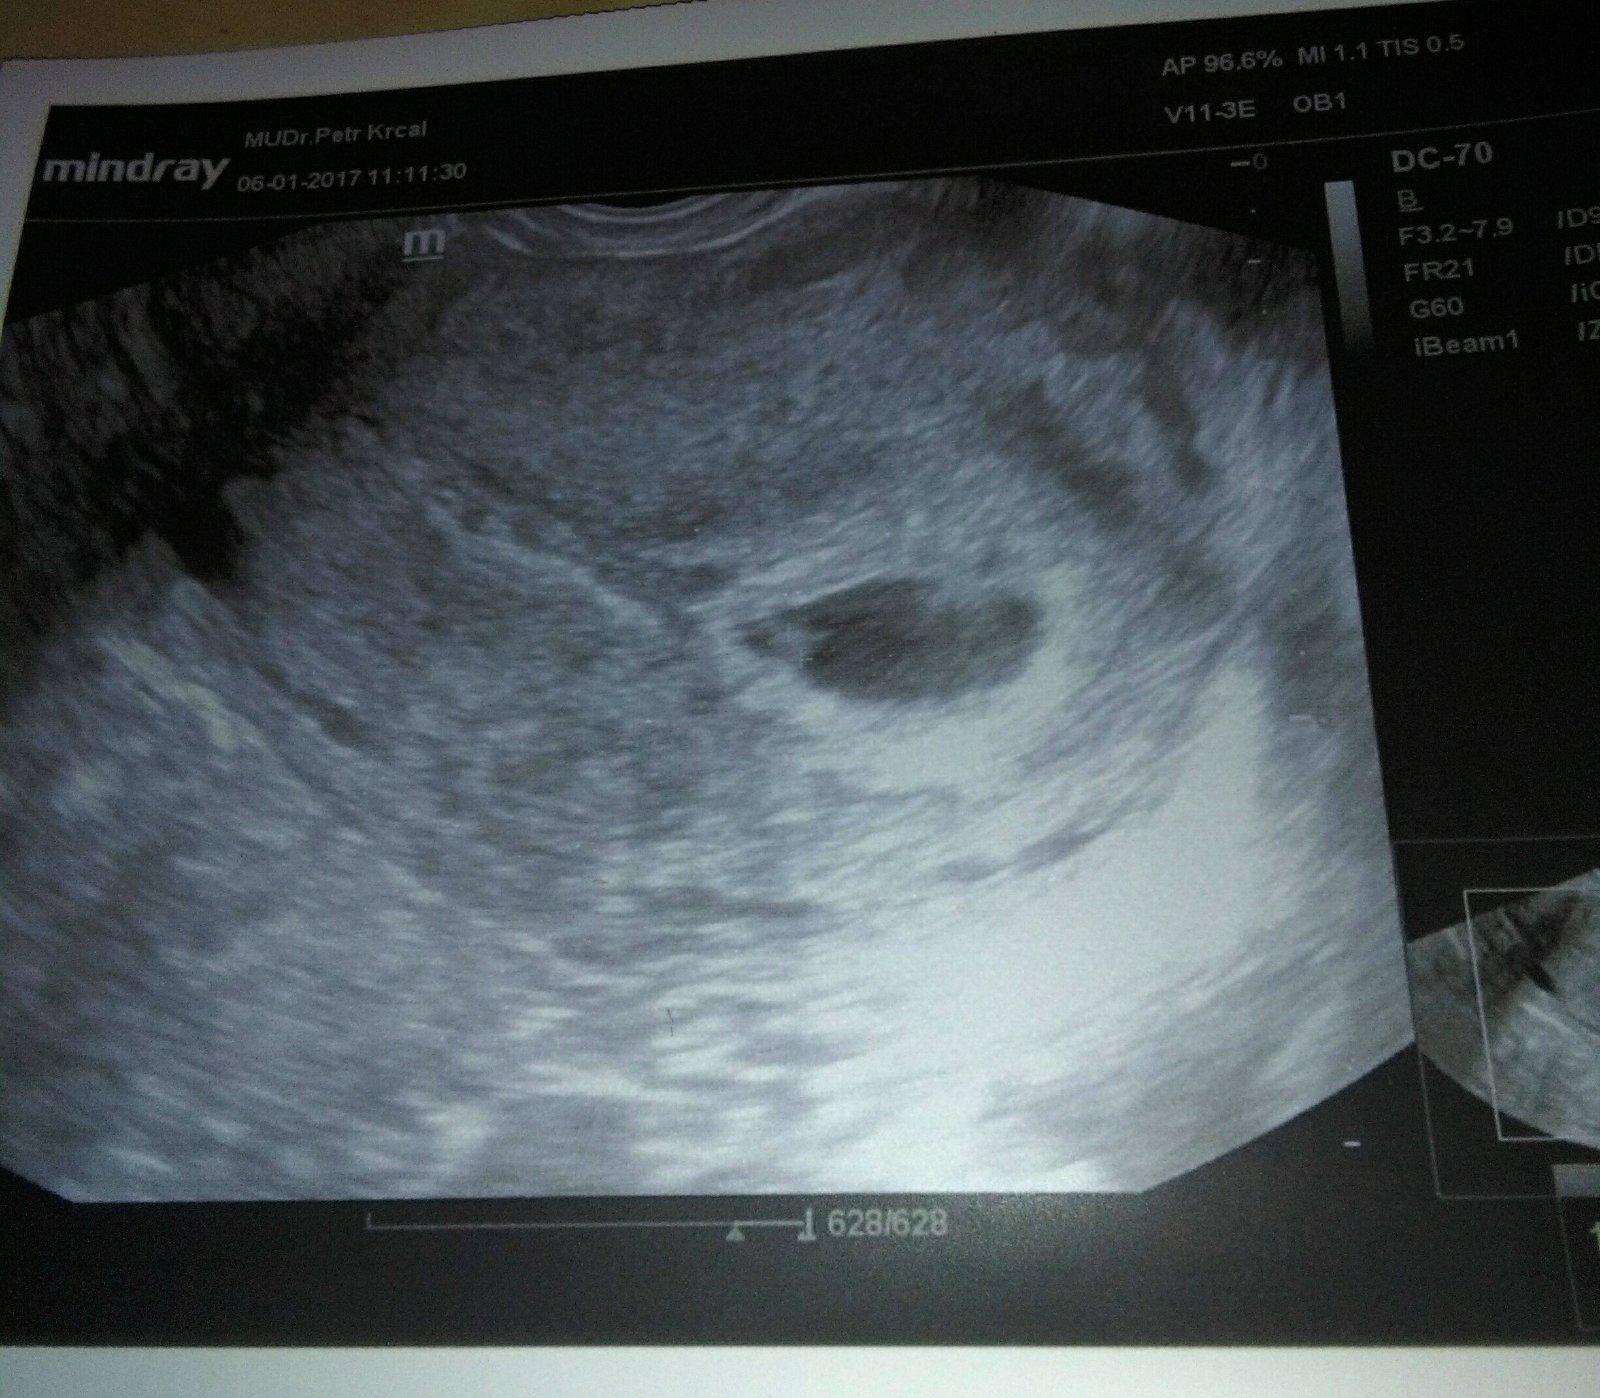

@simi1510 moc, děkuju 🙂 taky mi spadl kámen ze srdce. Přišla jsem na, řadu az asi po 3/4 hodině a to jsem byla, objednaná na, 10.30. tak to už byly nervy jak to dopadne. Prý tehdy když jsem byla tehu, to tam už, neviděl moc dobře, prý tam byly tri bubliny, který tam vubec neměli být, ale s, tímhle se to prý nedá vubec srovnat, prý to vypadá hodně nadějně a do 10 -14 dnů by mělo být srdíčko a,srdeční akce, tak za 14 dní doufám, že uz bude a vše bude jak má. To budou ještě větší nervy příště až tam budu.

A @laura1972 - krásný obrázek 🙂 Za 14 dní se těším zda bude srdíčko 🙂 Věřím, že ano, tak pfuj pfuj pfuj, ať jde vše jak má, a šetři se! 🙂